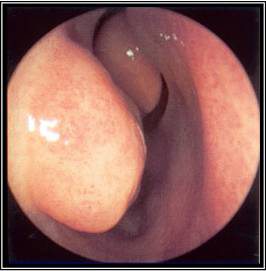

[Figure caption and citation for the preceding image starts]: Left middle meatus with healthy mucosa and non-purulent secretionsFrom the collection of Melissa Pynnonen, MD [Citation ends].

[Figure caption and citation for the preceding image starts]: Nasal endoscopy of the left nasal cavity showing a small polyp and pus in the middle meatusFrom the collection of Joseph K. Han [Citation ends].

The nasal cavity should be examined for the presence of mucosal erythema or purulent discharge. Optimal examination is performed after topical decongestant spray.[18] Either an otoscope or a nasal speculum and head light may be used. However, because nasal examination may be difficult or the signs non-specific, nasal endoscopy is recommended in selected patients, including patients refractory to empirical antibiotic therapy or where there is concern for antibiotic resistance, or in immunocompromised patients.

Endoscopy can provide excellent visualisation of the nasal cavity and sinus drainage paths. There are two types of endoscope: rigid and flexible. A rigid nasal endoscope has superior resolution and only requires the use of one hand. This easily allows cultures of the nasal cavity or sinus to be obtained if necessary. A flexible nasal endoscope is more comfortable for patients, but requires both hands to use. There are flexible nasal endoscopes that have a channel for collecting cultures, but these tend to be larger and more uncomfortable and they are also more difficult to re-process. Generally, the flexible nasal endoscope is preferred in children as it is better tolerated; however, either type may be used in adults and children. Choice will depend on the practitioner's familiarity with the procedure, and most will be performed by an ear, nose, and throat specialist.